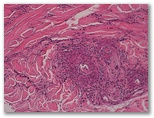

1566-R2-mácula purpurica

1. Síndrome de Schnitzler

2. Eritema elevatum diutinum fase tardía

3. Síndrome de Sweet

4. Granuloma facial